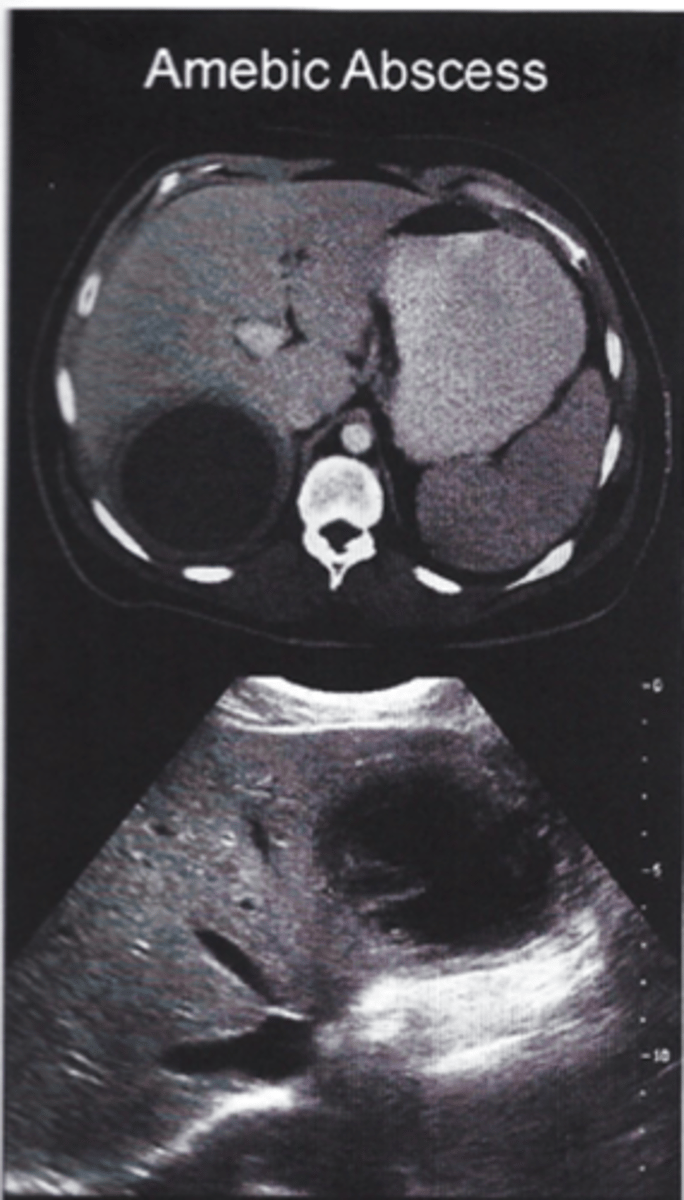

___ is a protozoan, which can cause amebic liver abscess single located in the right lobe liver.

Entamoeba hystolytica

- travel to Mexico, dysentery + RUQ pain with single cyst

- stool exam trophozoites, serology, liver imaging

- tx: Metronidazole

What confirms the dx of E. histolytica?

Serologic testing for E. histolytica antibodies